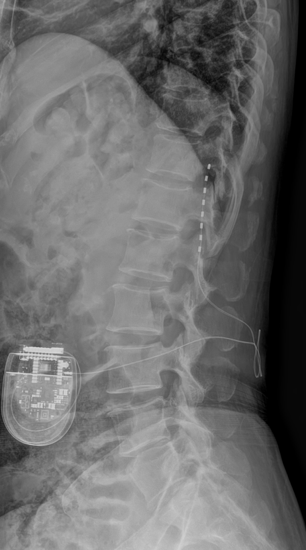

척수신경 자극술은 척수에 전기 자극을 주어 통증 신호가 뇌로 전달되는 것을 차단하거나, 나쁜 자극을 좋은 자극으로 바꿔주는 방식으로 통증을 완화시키는 치료법이다.

환자 척추에 미세한 전극을 삽입하고, 체내에 전기 신호를 제어하는 조절 장치를 이식해 통증을 조절할 수 있다. 전극을 삽입한 후에는 외부 프로그램을 통해 자극의 세기를 설정하고 테스트하는 과정을 거쳐 세밀하게 통증을 조절한다.